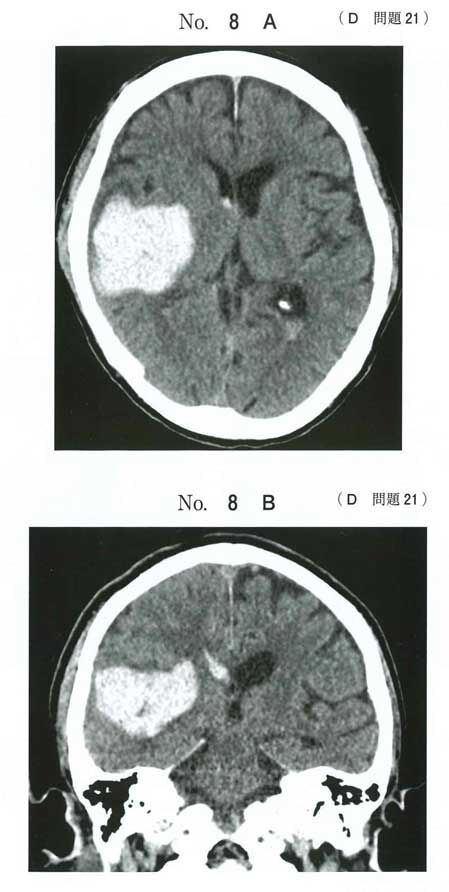

頭部単純CT水平断像(A)と冠状断像(B)とを次に示す。

この患者で認めるのはどれか。 (正答率:59.4%)

119D21(右被殻出血)出題の狙い

この症例は「脳出血の局在と神経症状を結び付けられるか」を問う問題です。 優位/非優位半球の症状差や被殻〜内包後脚・視放線の関係を、画像所見から症候に落とし込めるかが核心です。

右利き=左半球優位であることを前提に判断します。

2⃣ 次に、画像→局在→症候の対応付け

右被殻〜側頭葉に血腫 → 内包後脚を巻き込む → 左片麻痺・感覚障害

右半球病変なので、失語・失算・手指失認といった優位半球症状は原則出ない

血腫が側頭葉視放線(Meyer’s loop)へ及ぶ → 左同名上四半盲(広ければ同名半盲)

○ 左同名半盲(視野障害(c)) や左片麻痺 → 局在(右被殻〜内包後脚・視放線)と合致